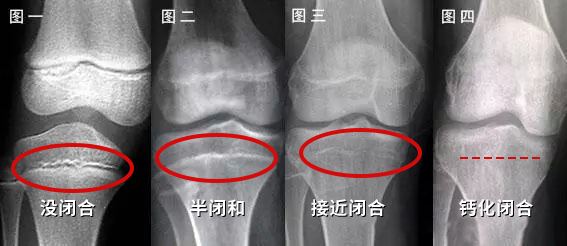

控制体重,减少体脂,延缓骨龄(脂肪含量高会分泌更多雌激素,加快生长发育,让骨骺线提前闭合)

75th以下建议做身高管理,而且越早管理效果越好。当然,不是所有的孩子来场馆做身高管理,你都要给他做,一般来说孩子成长板消失,骨骺线闭合(男16岁,女14岁),就没有长高空间。